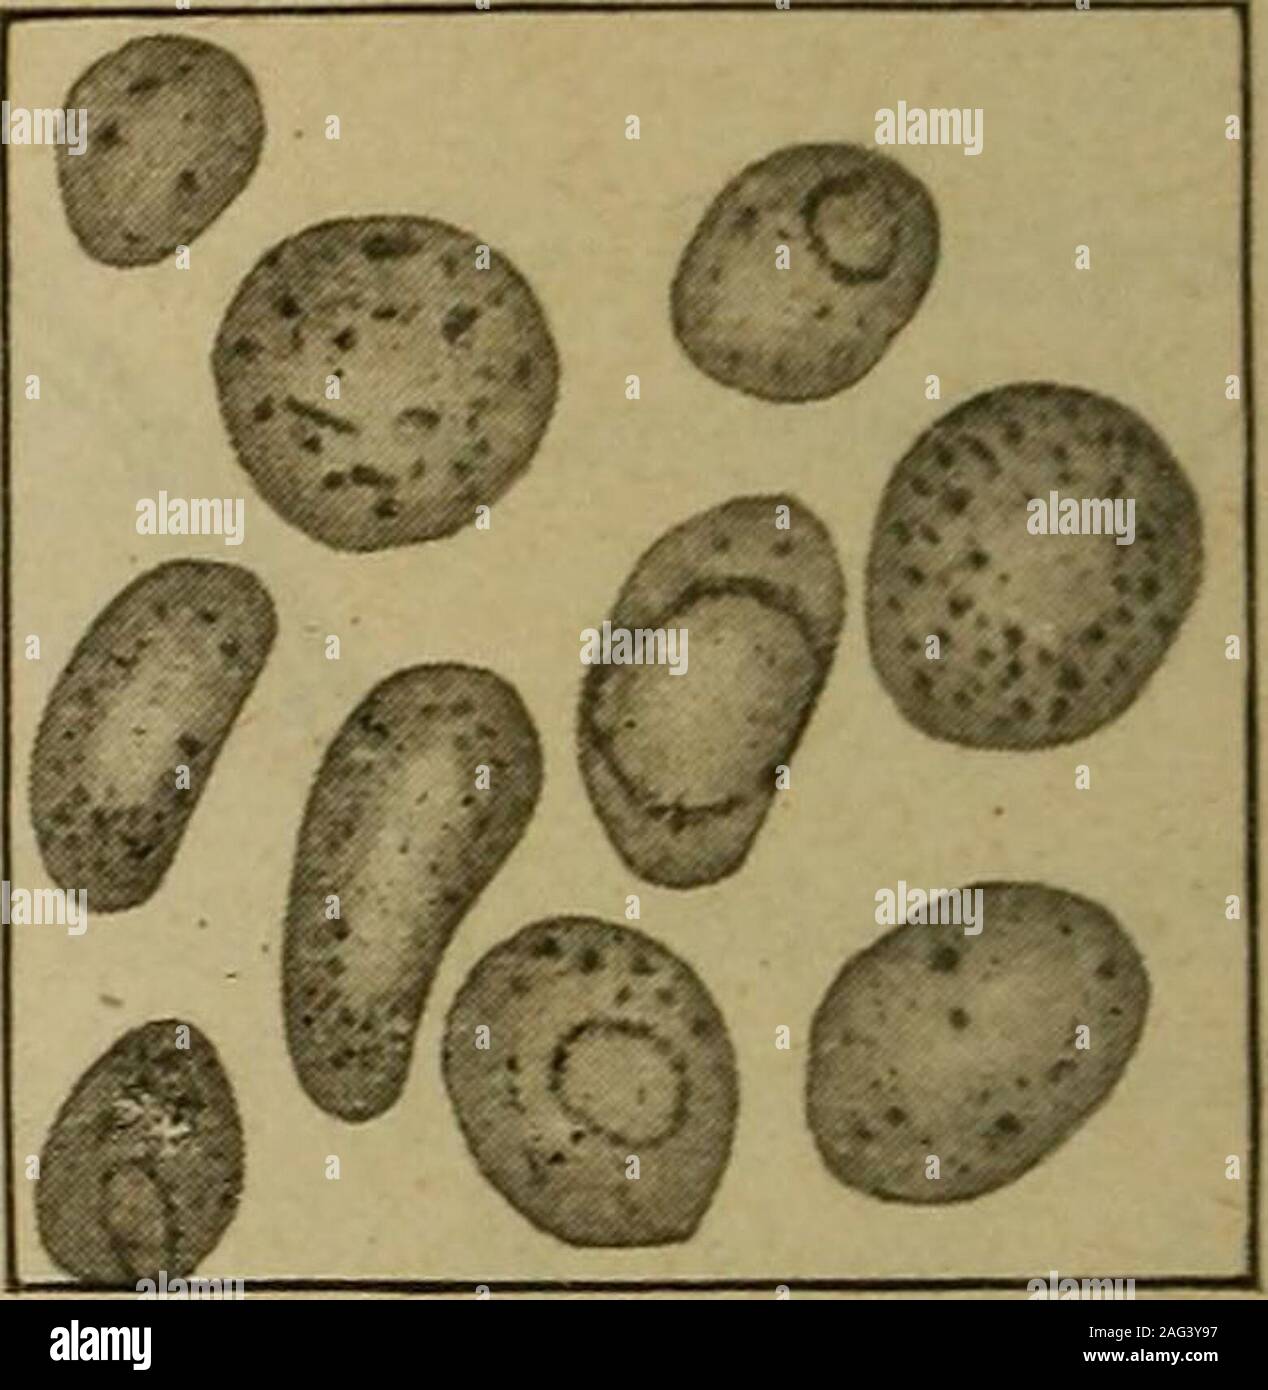

RM2AG3Y97–. Medizinische Diagnose für die Studierenden und Praktiker. epresents Defekt hemogenesis und bedeutet Degeneration, beingfound als vorherrschende Art der erythroblast nur in primären perniziöse Anämie, Nitro-benzol Vergiftung und bothriocephalus Anämie. In jedem schwere Anämie anoccasional Zelle dieser Art gefunden werden kann. Ich Die microblast (5 bis 6 ju) stellt im Wesentlichen das gleiche Aussehen, abgesehen Ifrom Größe, wie dem normoblast und hat die gleiche klinische Bedeutung. Ungewöhnliche Formen. - Verschiedene Mischformen auftreten (mesoblasts) | Die Differenzierung zu trotzen, die Widersprüche in Größe und Färbung Mes